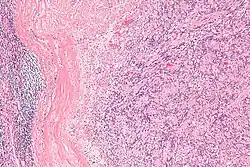

IPMs are diagnosed by examination of the tissue by a pathologist. They have a rim of peripheral lymphoid tissue (remnant of a lymph node) and consist of spindle cells with nuclear palisading. Red blood cell extravasation is common and blood vessels surrounded by collagen with (fine) peripheral spokes (amianthoid fibers) are usually seen.[2]

Immunostains for smooth muscle actin and cyclin D1 are characteristically positive. The main histologic differential diagnosis is schwannoma.

Low mag. -